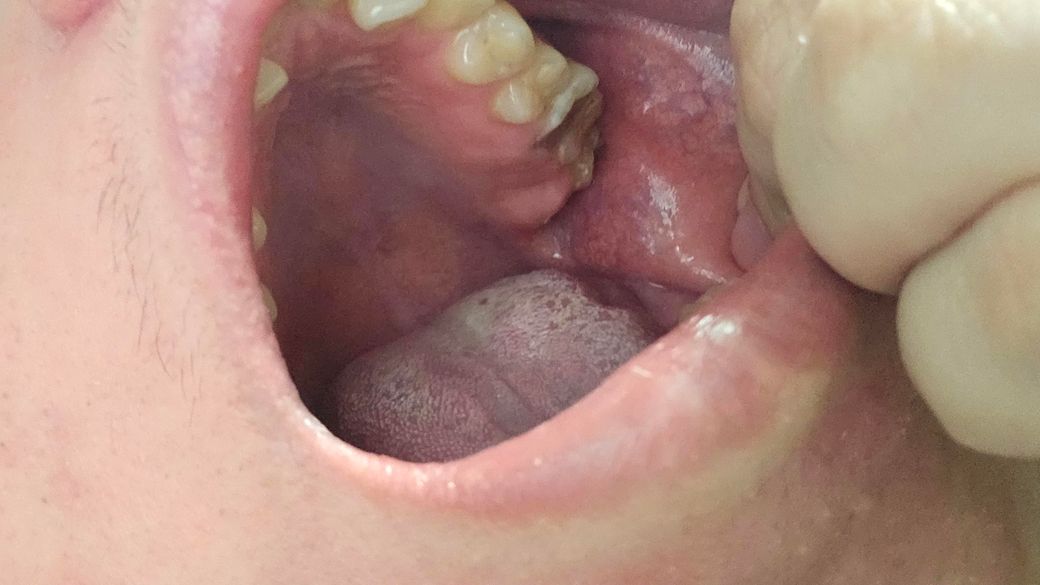

제가 6월아니면 7월에 치과 갔는데요 조금 늦게 갔는것가요? 이쪽 이빨 이상태인데요

• 2번 째 사진

사진상으로 치아가 깨진것처럼 보입니다 치아가 깨졋거나 충치가 진행된 상태라면 최대한 빨리 가시는게 좋습니다.

치아의 많은 부분이 충치로 인해서 손상된것으로 보입니다. 빠른 치료가 필요할거으로 보이며 충치가 치아의뿌리까지 진행이 되었다면발치를 해야 할수 있습니다.

사진상 보이는 어금니의 경우 충치가 깊어보여서 신경치료 등 치료보다는 발치가능성 높습니다